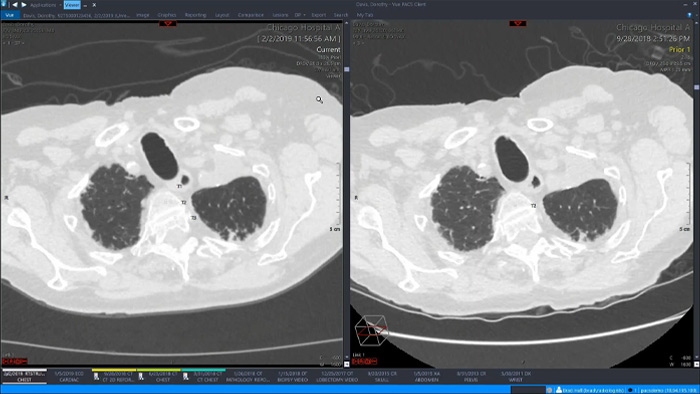

Let’s take a look at some of the immediate benefits of a unified approach. A single, unified workspace for radiology would incorporate advanced 3D post-processing and image distribution capabilities, opened in an additional viewer tab for ease.

A unified workspace would mean that users can easily launch the relevant analysis tools from among the 70+ advanced applications available across multiple clinical domains. Artificial Intelligence can play a role by automating tasks and workflows, predicting usage patterns.